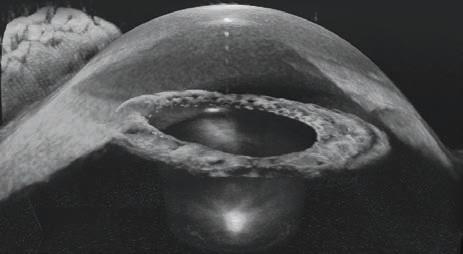

HP-OCT OFFERS ‘PARTICULAR ADVANTAGES IN THE ANTERIOR SEGMENT’

Cylite is an Australian-based company developing the next generation of diagnostic OCTs for optometry and ophthalmology. The company’s Hyperparallel OCT (HP-OCT) is a world-first, capturing accurate volumetric data of the eye, with particular advantages in the anterior segment.

“Scanning at an industry-leading 302,400 A-scans per second, the technology simultaneously images across a wide area of the eye with minimal motion artefacts, allowing the production of highly accurate and repeatable elevation and curvature maps, as well as accurate analytics to enable clinicians to make more informed decisions for better patient outcomes,” Cylite states.

According to the company, in one scan, the HP-OCT captures a full 3D image of the anterior segment, which can be used for personalised contact lens fitting, as well as a full set of biometric measurements, including axial length, for use in myopia management. The same volumetric imaging technique can also be applied to the posterior segment to produce excellent volumetric retinal images.